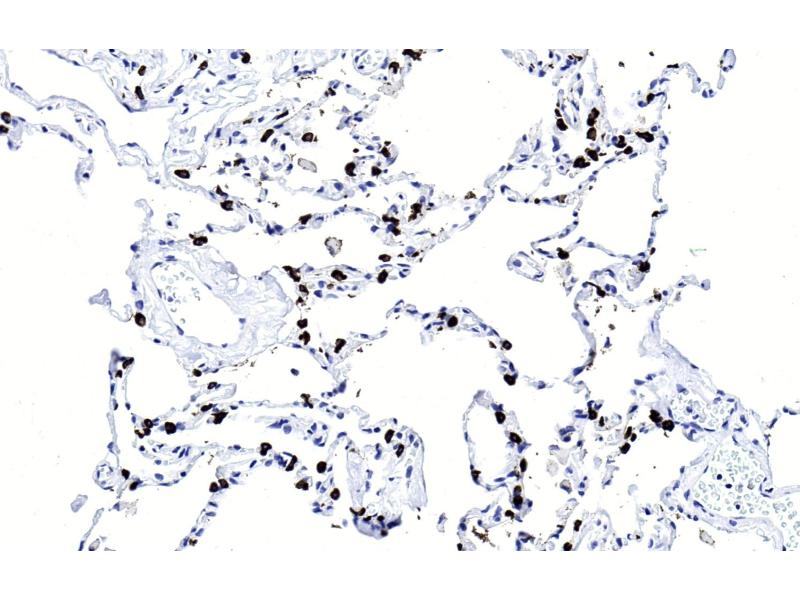

Surfactant Protein C Antikörper

(Surfactant Protein C (SFTPC))

Wählen Sie einen von 82 Surfactant Protein C-Antikörpern aus unserem Produktangebot basierend auf 7 Publikationen und 54 Validierungsbilder.

Entdecken Sie zuverlässige Surfactant Protein C-Antikörper von einer großen Zahl namhafter Hersteller. Unser Portfolio ermöglicht eine präzise Surfactant Protein C-Detektion in verschiedenen Spezies, darunter Human, Mouse, Rat, Cow, Dog, Guinea Pig, Horse, Rabbit, Sheep, und unterstützt vielfältige Forschungsanwendungen wie WB, ELISA, IF, IHC, FACS.